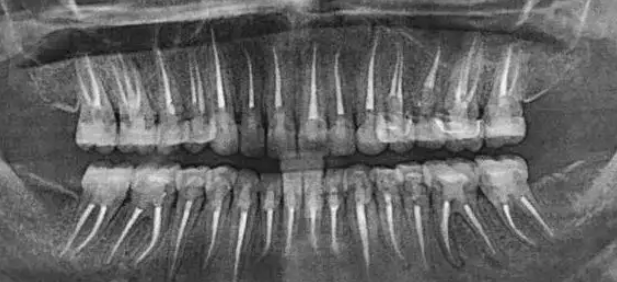

牙医需警惕:一张牙片,“救”了诊所,也救了患者!